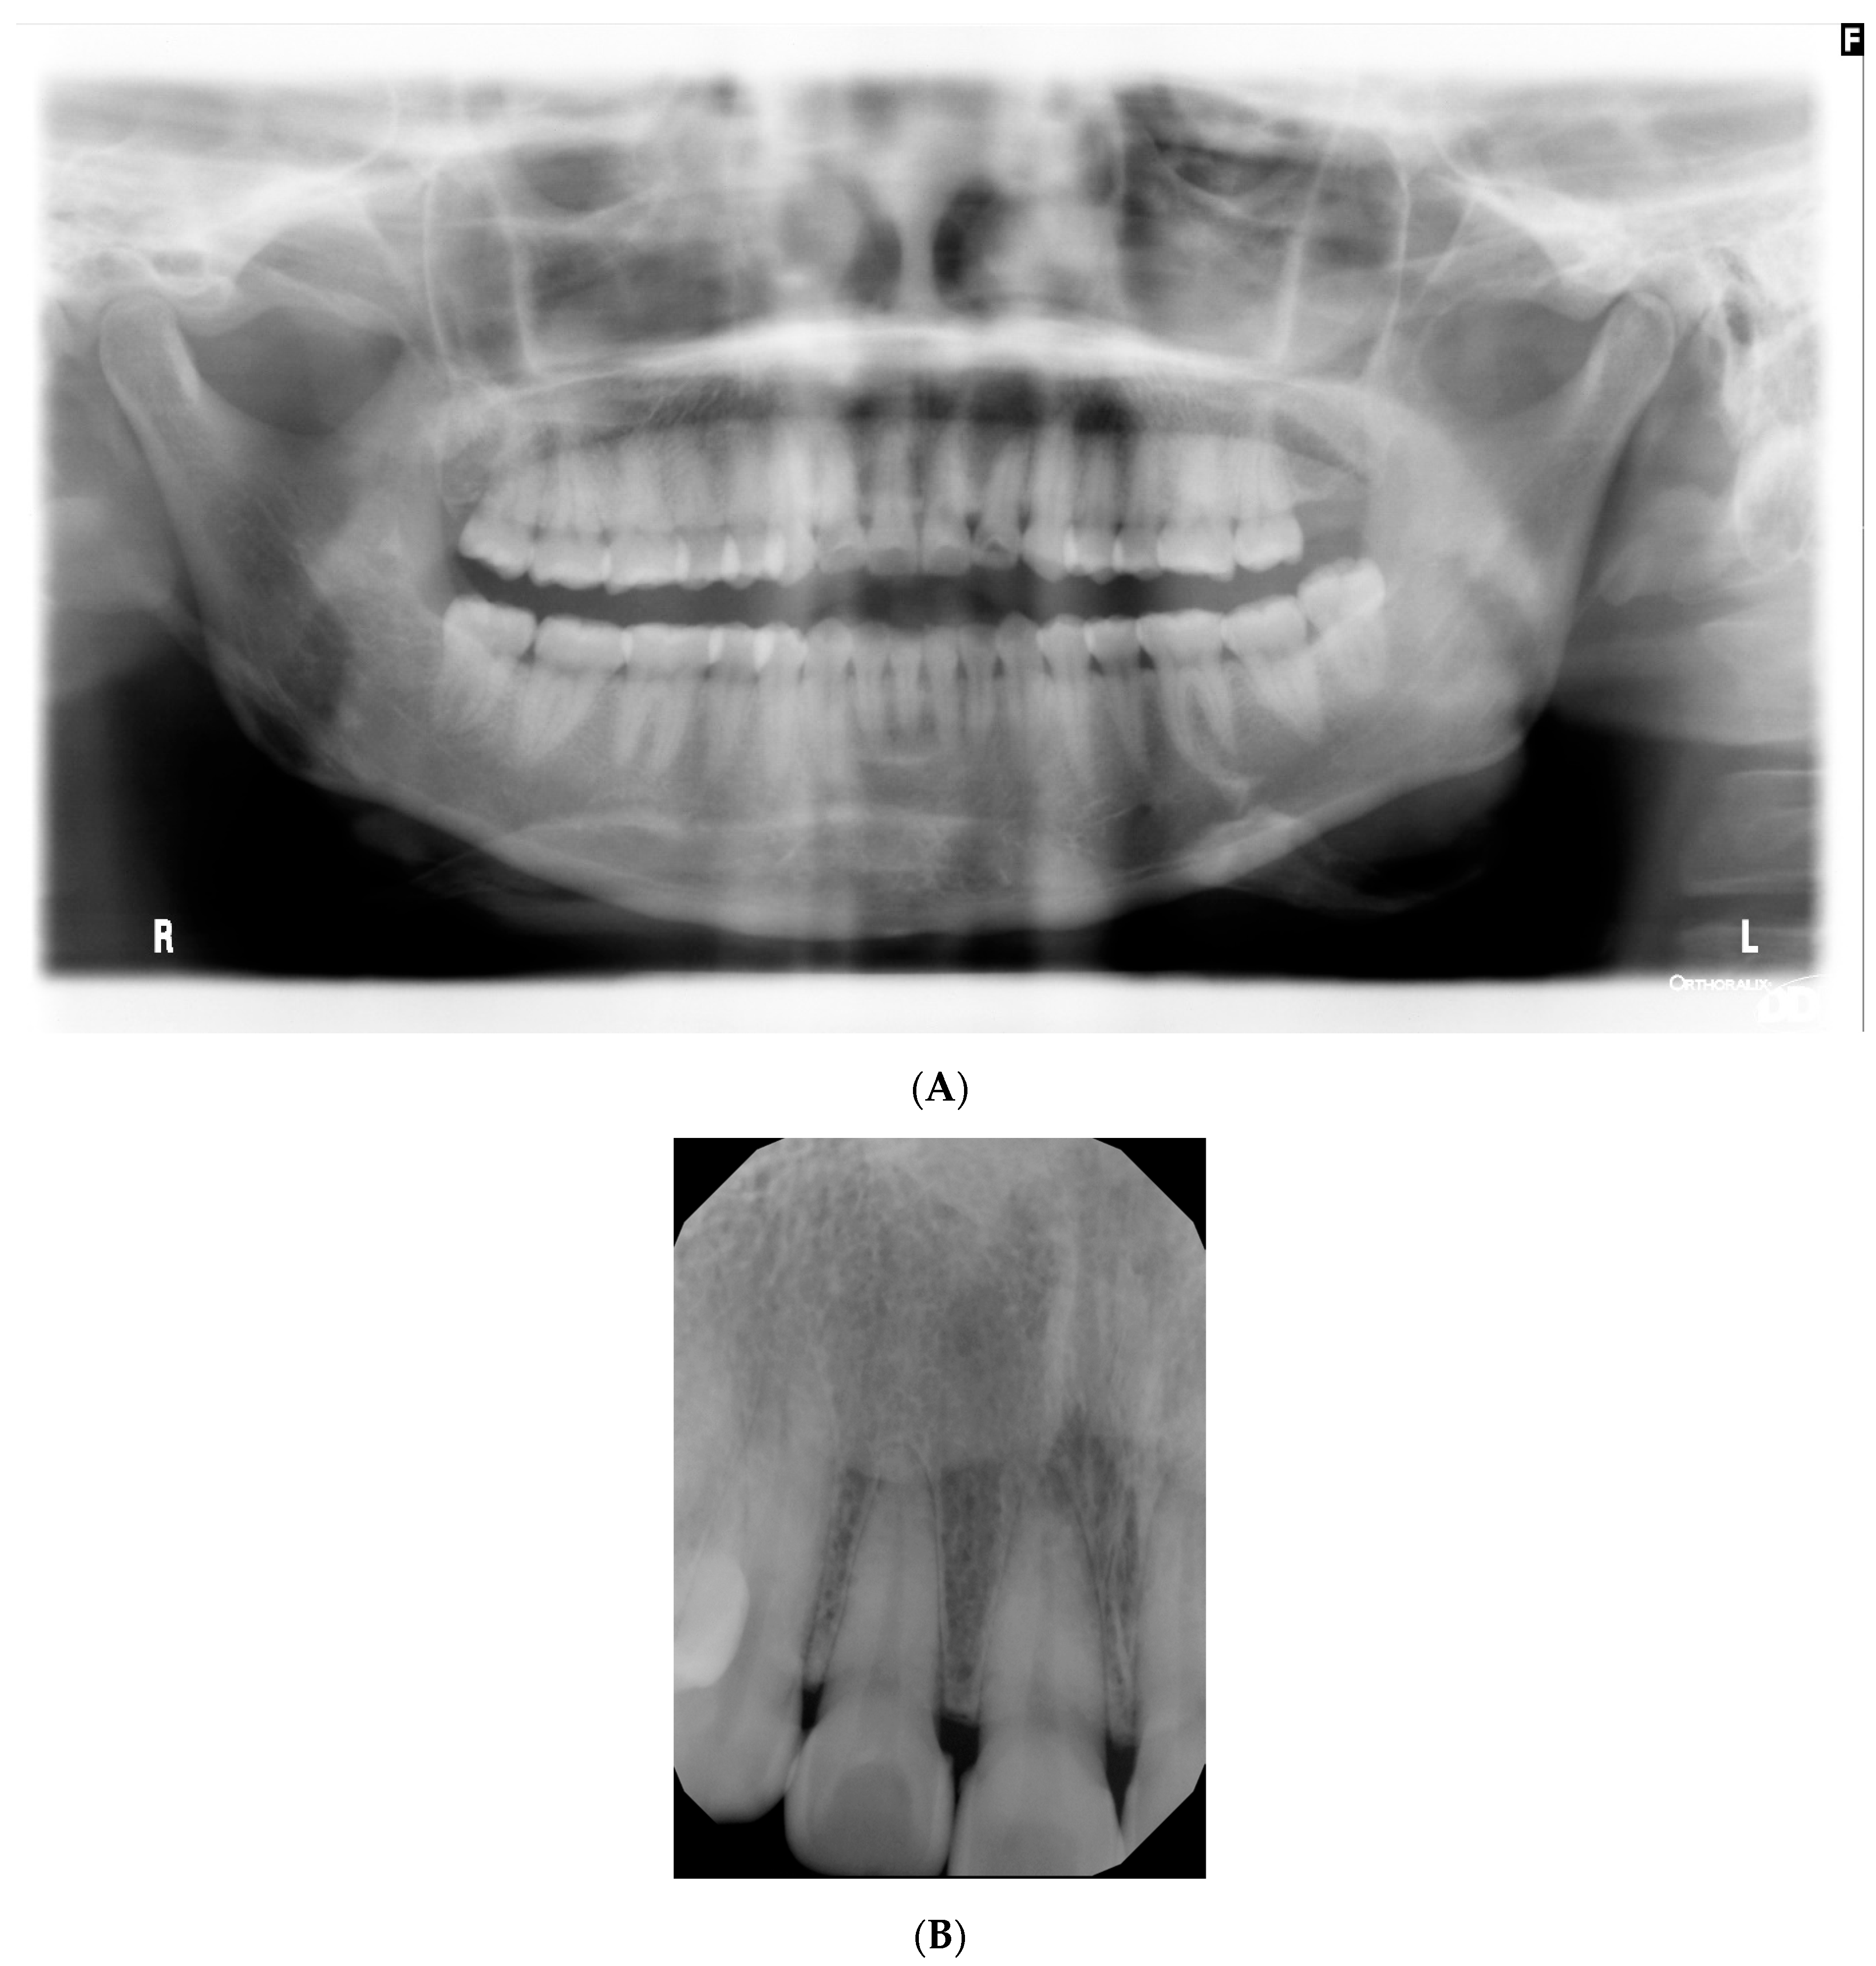

2. Case Presentation